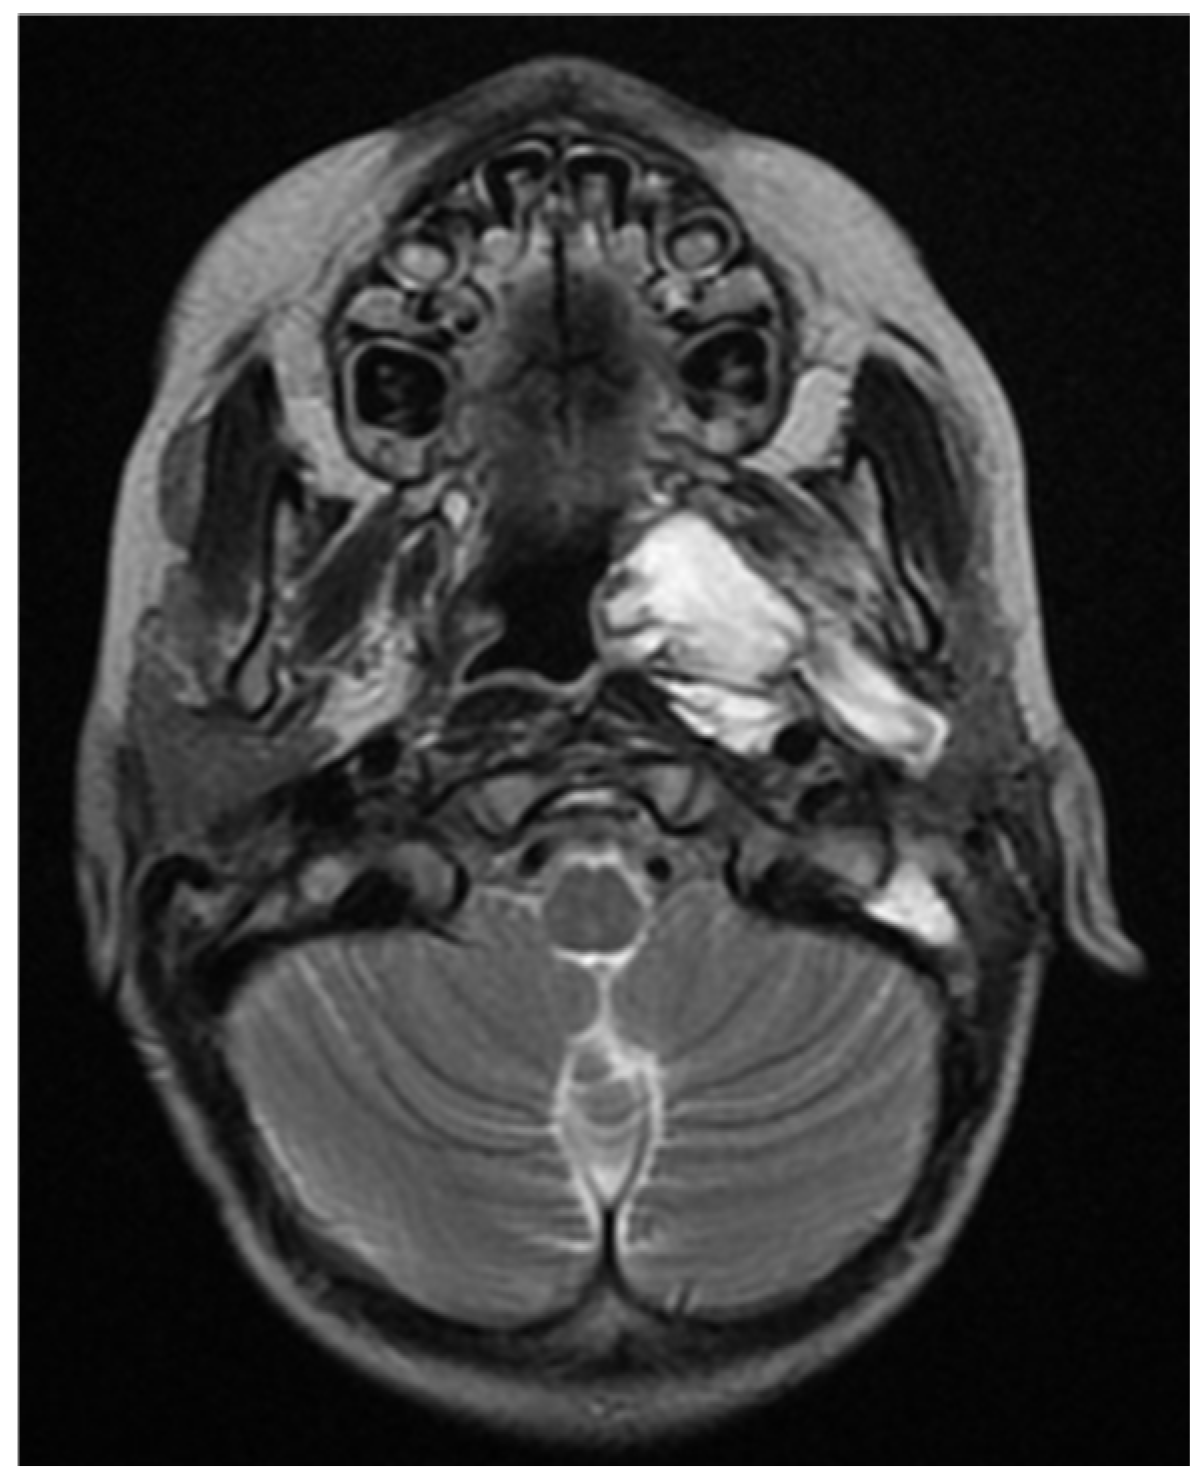

A CNS MRI was performed, which reveal a large lobulated formation in the oropharynx and nasopharynx with left tonsil involvement, spreading to the retropharyngeal space and propagating through the left Eustachian tube into the middle ear. The previously formed surgical cavity was completely infiltrated from the soft tissue tumour mass. Approximate dimensions of the lesion in the mastoid—25/45 mm. axial, 38/39 mm. coronal (Figure 6, Figure 7 and Figure 8).

Figure 6. MRI of the patient on postoperative day 17.

Figure 7. MRI of the patient on postoperative day 17.

Figure 8. MRI of the patient on postoperative day 17.